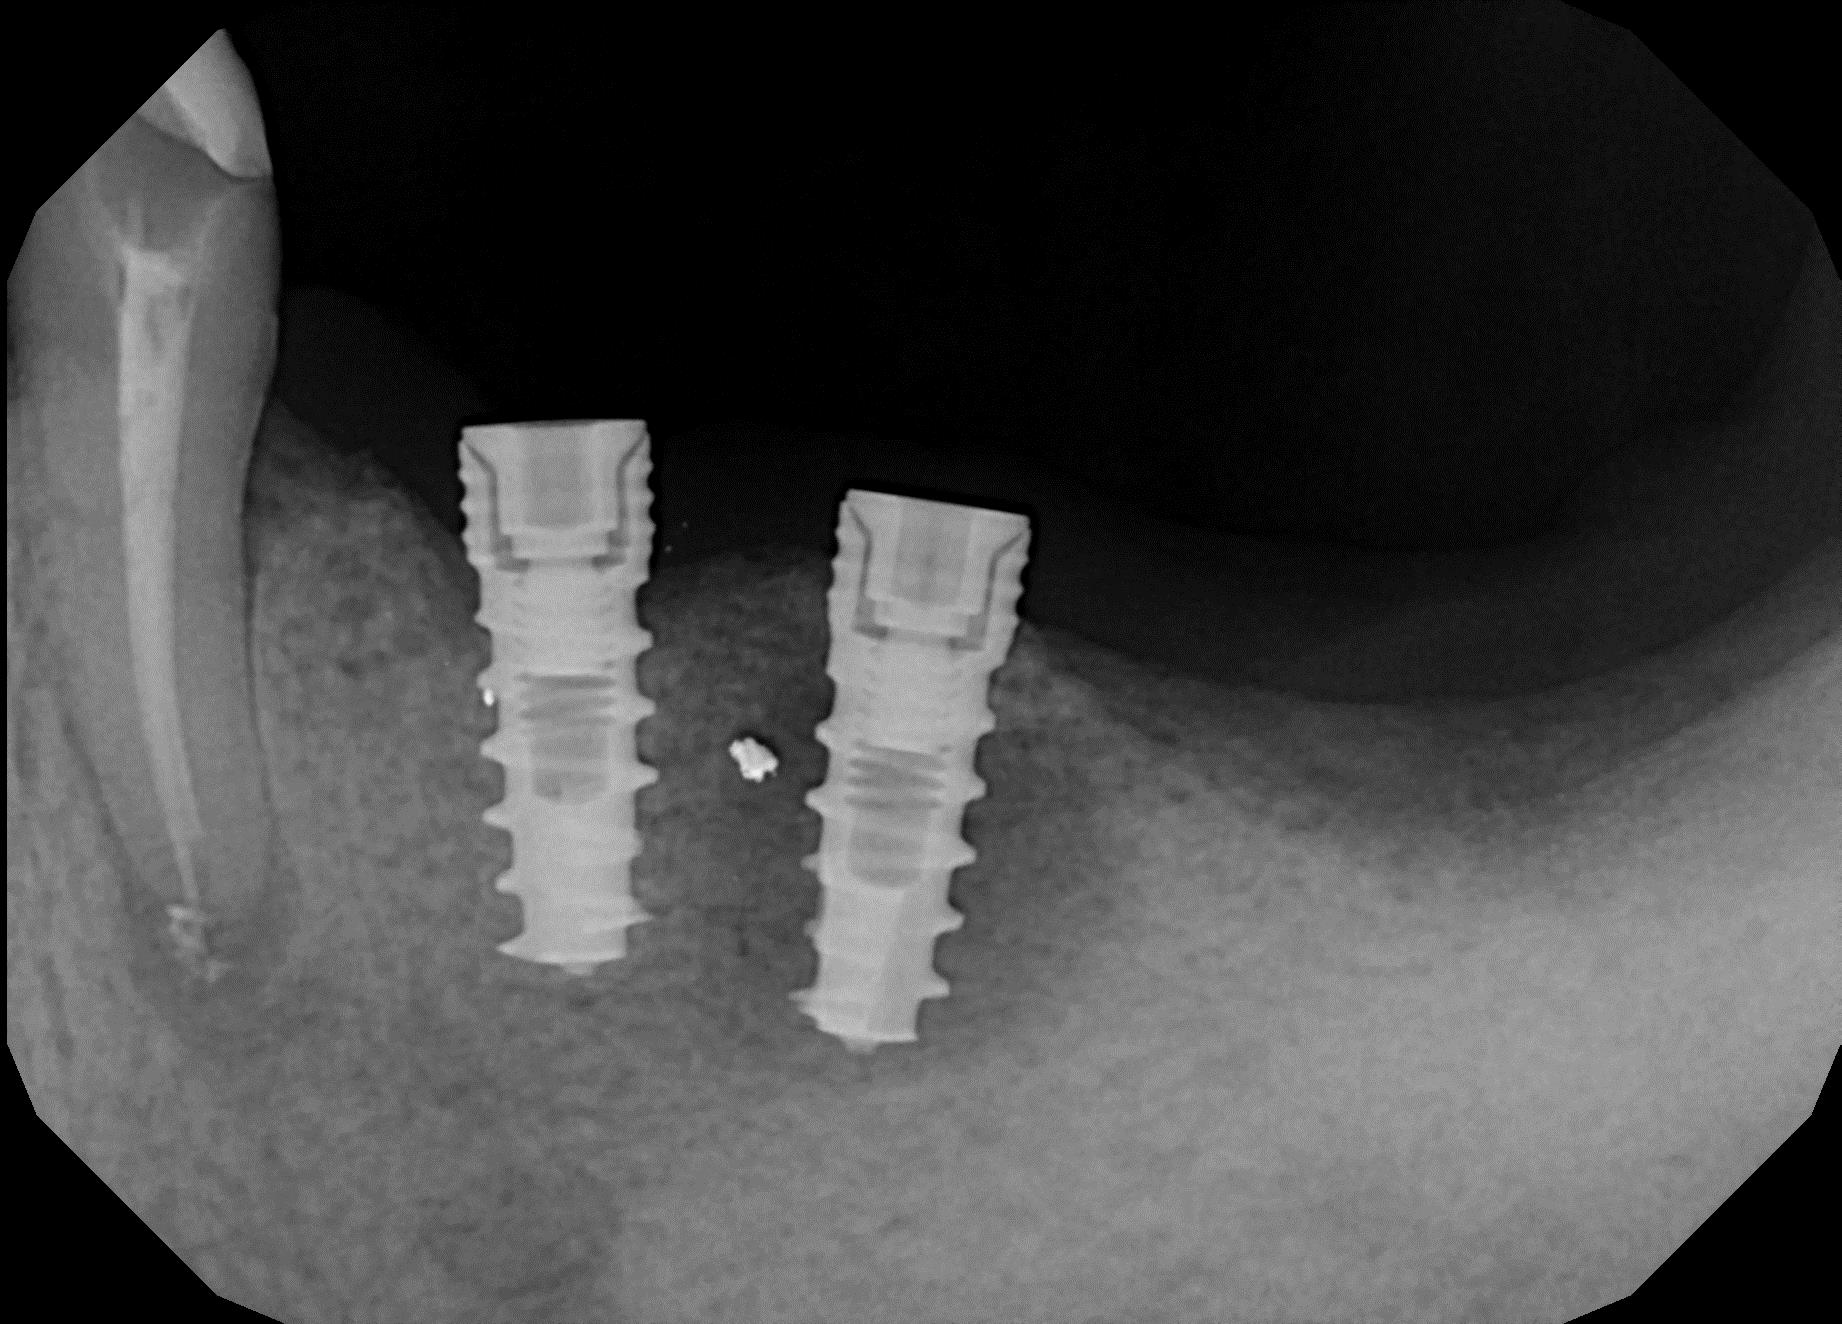

При постановке диагноза стоматолог собирает подробный анамнез, проводит полный осмотр ротовой полости и проводит рентгенологическое исследование.

Наиболее информативными диагностическими аппаратными методиками являются прицельная рентгенография, ортопантомография, а также компьютерная томография, позволяющие выявить наличие и степень резорбции костных структур. В качестве дополнительных методик применяются лабораторные методы исследования – полимеразная цепная реакция, бактериологическое исследование и определение рН жидкости полости рта.